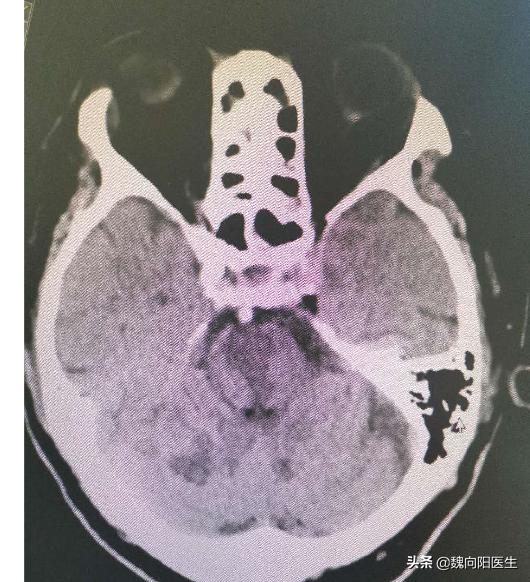

椎基底动脉延长扩张综合征:指的是椎基底动脉延长、迂曲、扩张,导致脑干、脑神经受压或动脉内血栓形成和血管破裂引起脑梗死或脑出血。

- 扩张:基底动脉直径>4.5mm 或 椎动脉直径>4mm

- 延长:基底动脉上段超过床突平面6mm以上,BA长度大于29.5mm

- 迂曲:BA横向偏离超过起始点至分叉之间垂直连线1mm。